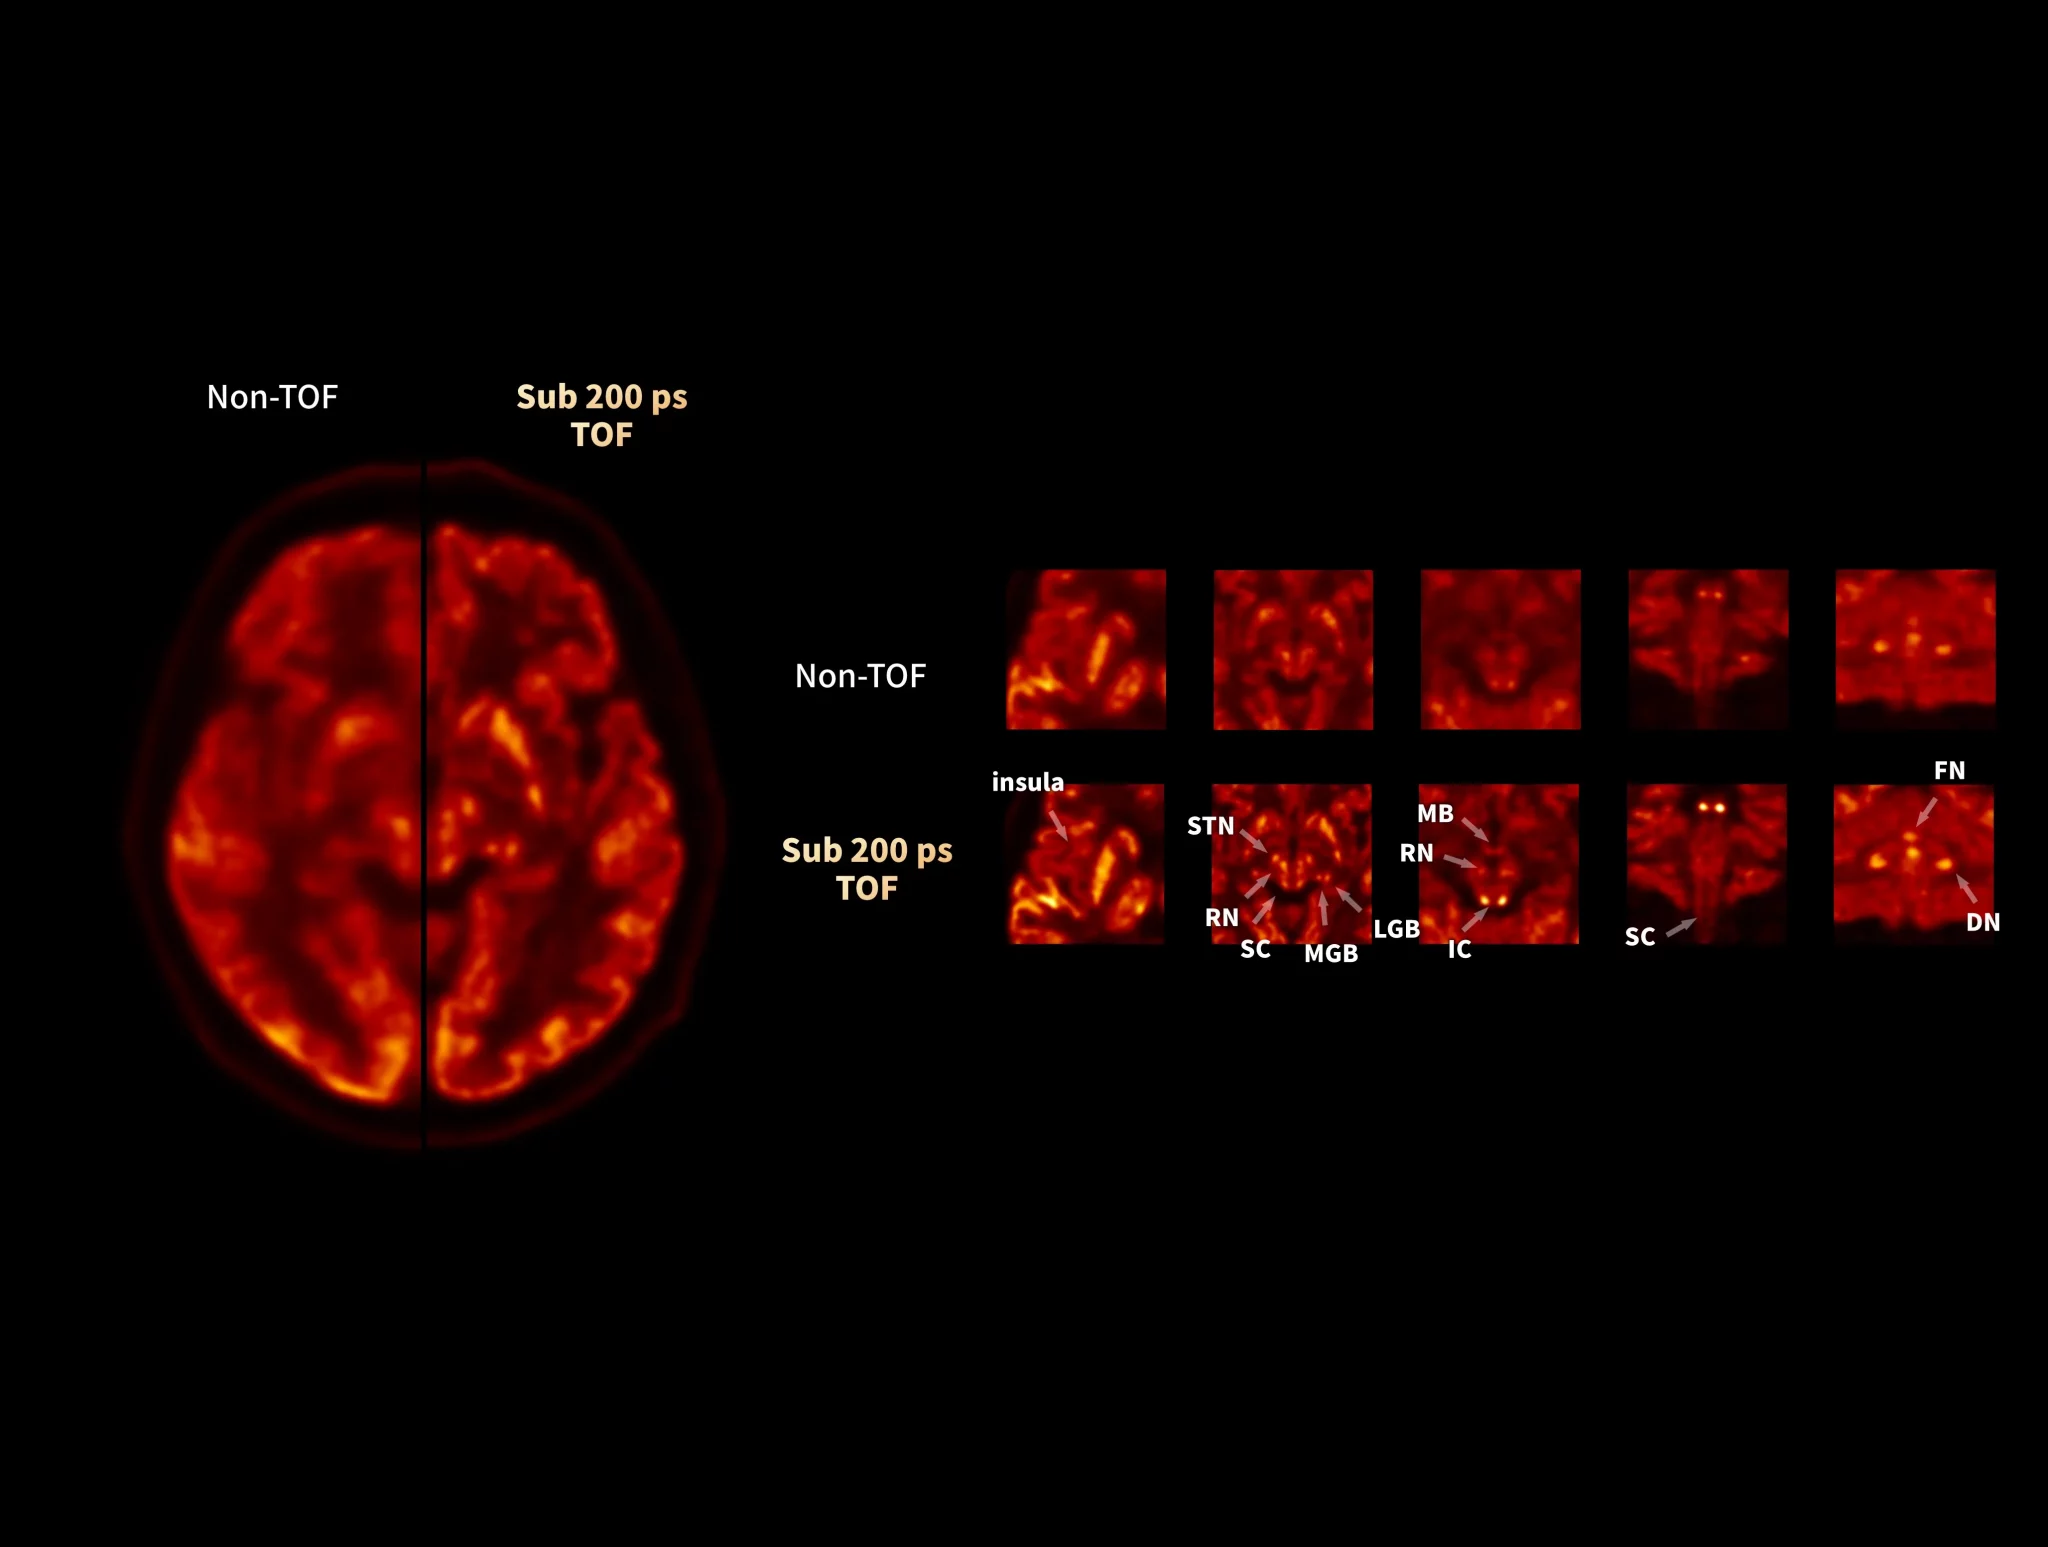

uMI Panorama is clearly magnificent in every direction with the finest National Electrical Manufactures Association (NEMA) PET spatial resolution, truly-fast 189-picosecond (ps) time of flight (TOF), scalable axial field of view (AFOV), the 76-cm super-wide bore and 318-kg (700-lb) table weight capacity that accommodates patients of all sizes.1 By leveraging the AI-powered features on the uExcel platform, it also boosts your daily work efficiency significantly and opens up new possibilities for your exploration.

With the ultra-high system performance, uMI Panorama faces up to the challenges of tracers with different half lives and the complex scanning conditions, without compromise for image quality.